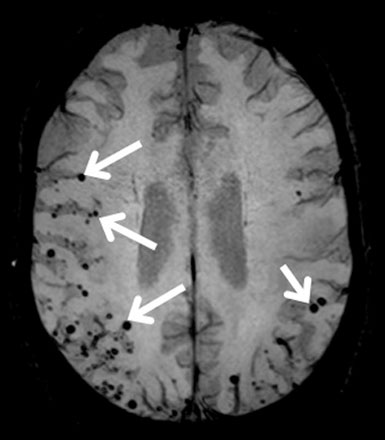

МРТ амилоидной ангиопатии. Белыми стрелками обозначены микрокровоизлияния, которые возникли в следствии отложения амилоидного белка